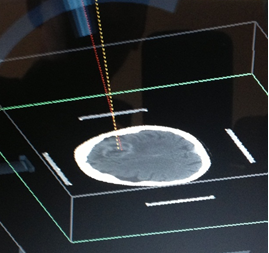

1) MARCO ESTEREOTAXIA: Marcación estereotáctica para lesiones profundas , craneotomias guiada por estereotaxia y/o asistidas por Neuronavegación. (Incluirá el equipo)